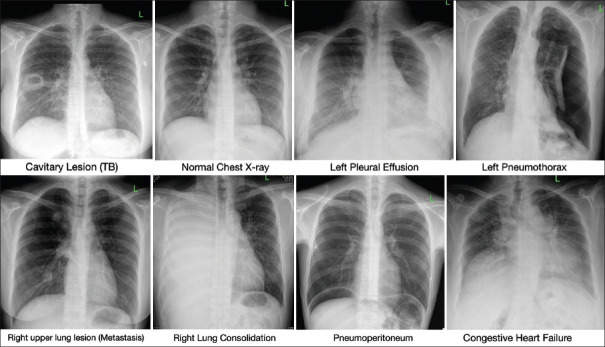

Abstract Image